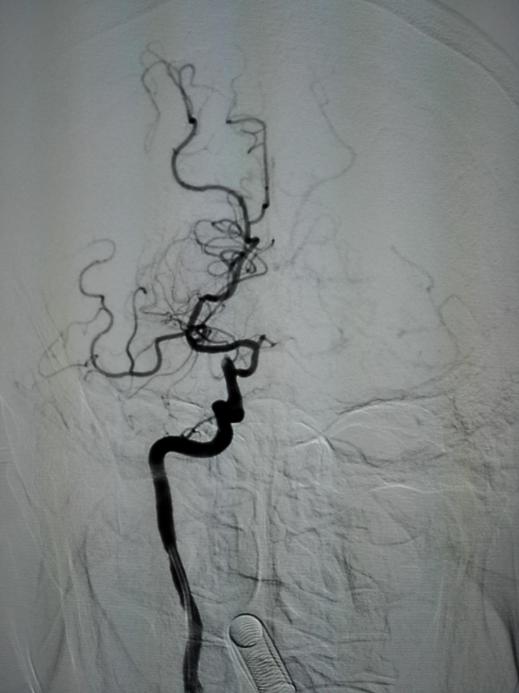

手术相关图片:

取出的栓子